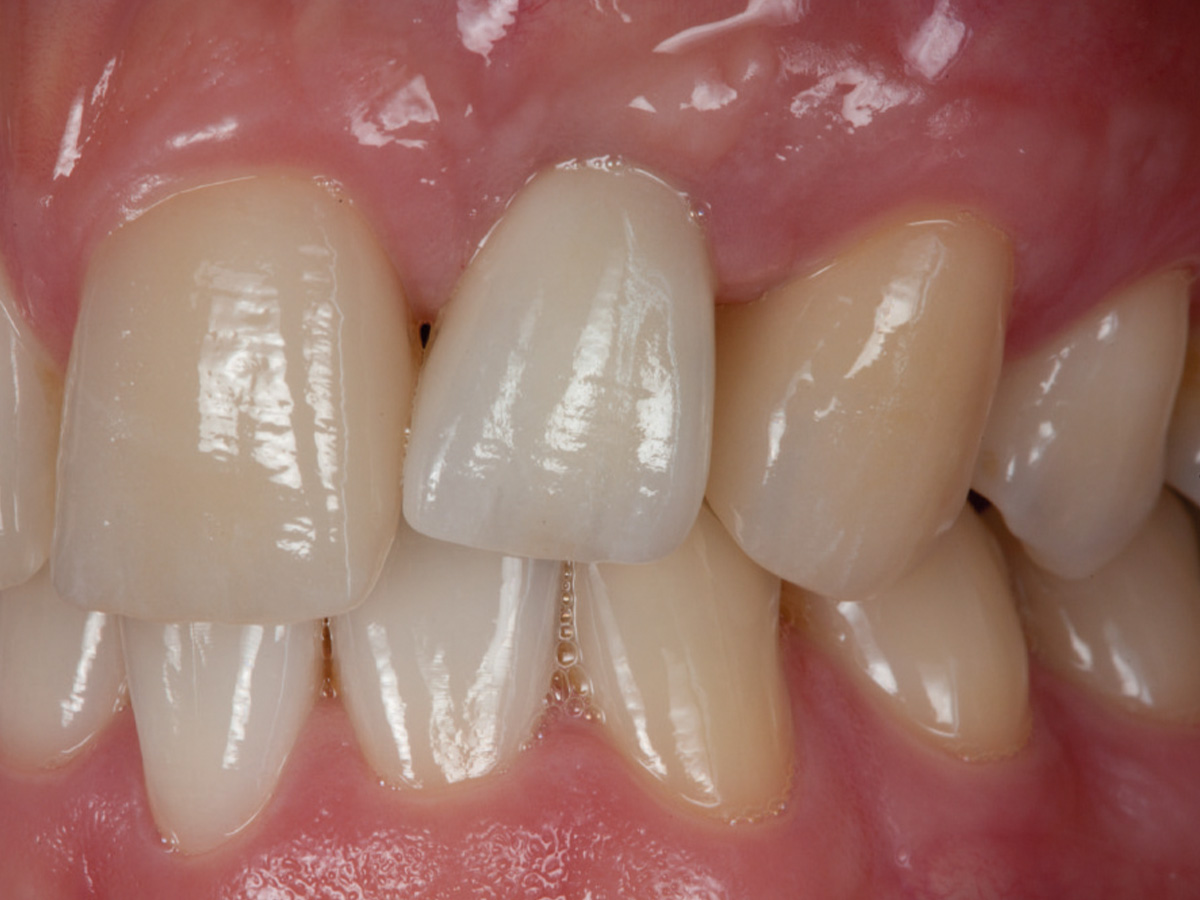

Abbildung 8

6 Monate nach der Augmentation.